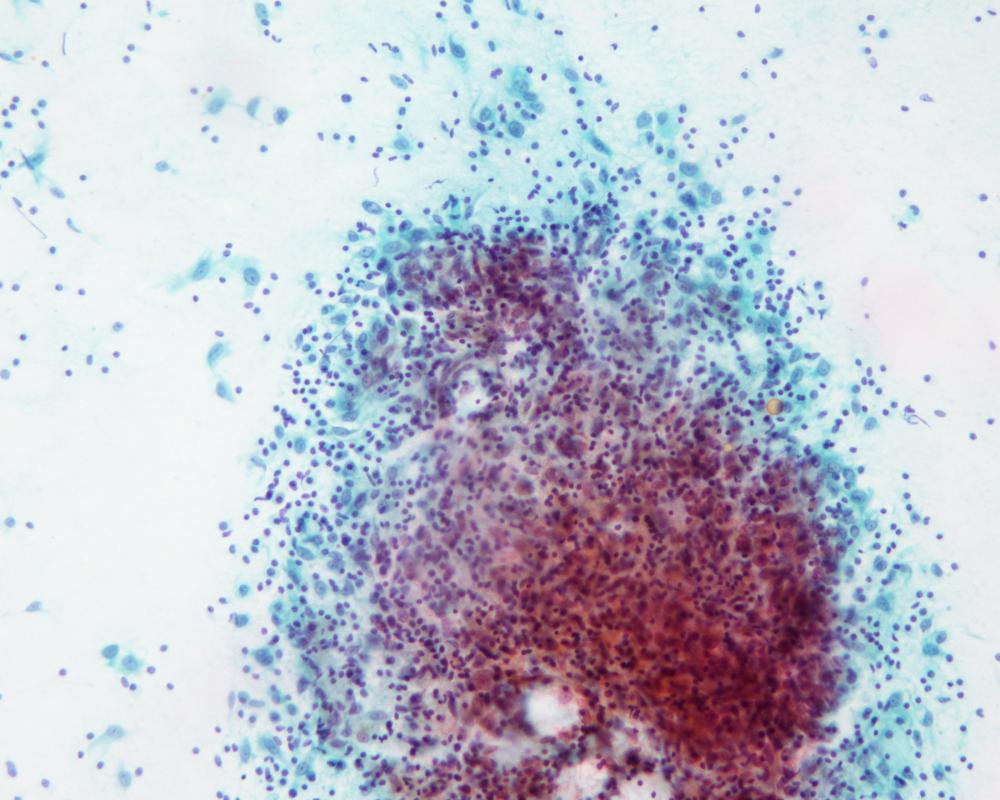

第36回日本臨床細胞学会九州連合会学会(大分)スライドカンファレンス症例2

種別:呼吸器

出題:長崎大学大学院医歯薬学総合研究科 病理学 林 洋子

| 年齢 | 60代 | 性別 | 男性 |

| 採取部位 | 肺 | 採取方法 | 術中穿刺 |

| 検体処理法 | 直接塗抹 |

臨床所見

【既往歴】 2年前に肺腺癌にて左上葉切除術後

【現病歴】 術後経過観察目的の胸部CTにて右肺下葉S9に、径15mm大の結節を認めた。1年前のCTでは径6mm大であり、増大傾向が認められた。画像的に、転移よりは他の原発性肺腫瘍が疑われた。

| 正解 | 5.炎症性線維芽細胞性腫瘍 |

▼選択肢及び投票結果

| 1.腺癌 | 1件 | (1.6%) | |

| 2.扁平上皮癌 | 1件 | (1.6%) | |

| 3.肉腫様癌 | 10件 | (15.6%) | |

| 4.カルチノイド | 0件 | (0.0%) | |

| 5.炎症性線維芽細胞性腫瘍 | 52件 | (81.2%) | |

| 投票総数 | 64件 | (100%) |